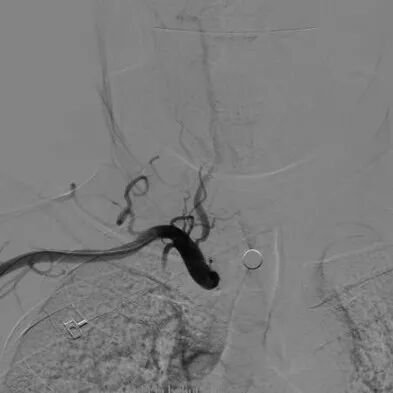

手术过程

--沿保护伞导丝引入波科4mm*30mm-Sterling球囊跨狭窄段扩张后,交换9mm*40mm-Wallstent支架经波科7F导引导管顺利到达狭窄段,跨狭窄段缓慢平稳释放。

-- 支架释放后残余狭窄稍高,再次交换引入波科4mm*30mm-Sterling球囊行支架内后扩张,使用5F 125cm多功能回收保护伞,复查造影示狭窄明显改善,前向血流通畅。

-- 术后即刻正侧位造影示左侧颈内起始部狭窄明显改善,支架内血流通畅,远端分支显影正常。